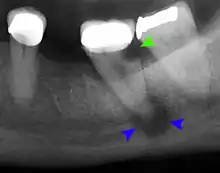

The periodontal ligament becomes inflamed and there may be pain when biting or tapping on the tooth. On an X-ray, bone resporption appears as a radiolucent area around the end of the root, although this does not manifest immediately.[10]:228 Acute apical periodontitis is characterized by well-localized, spontaneous, persistent, moderate to severe pain.[6]:125–135 The alveolar process may be tender to palpation over the roots. The tooth may be raised in the socket and feel more prominent than the adjacent teeth.[6]:125–135

Decay (green) with apical abscess (blue)

Gutta-percha point indicating abscess origin